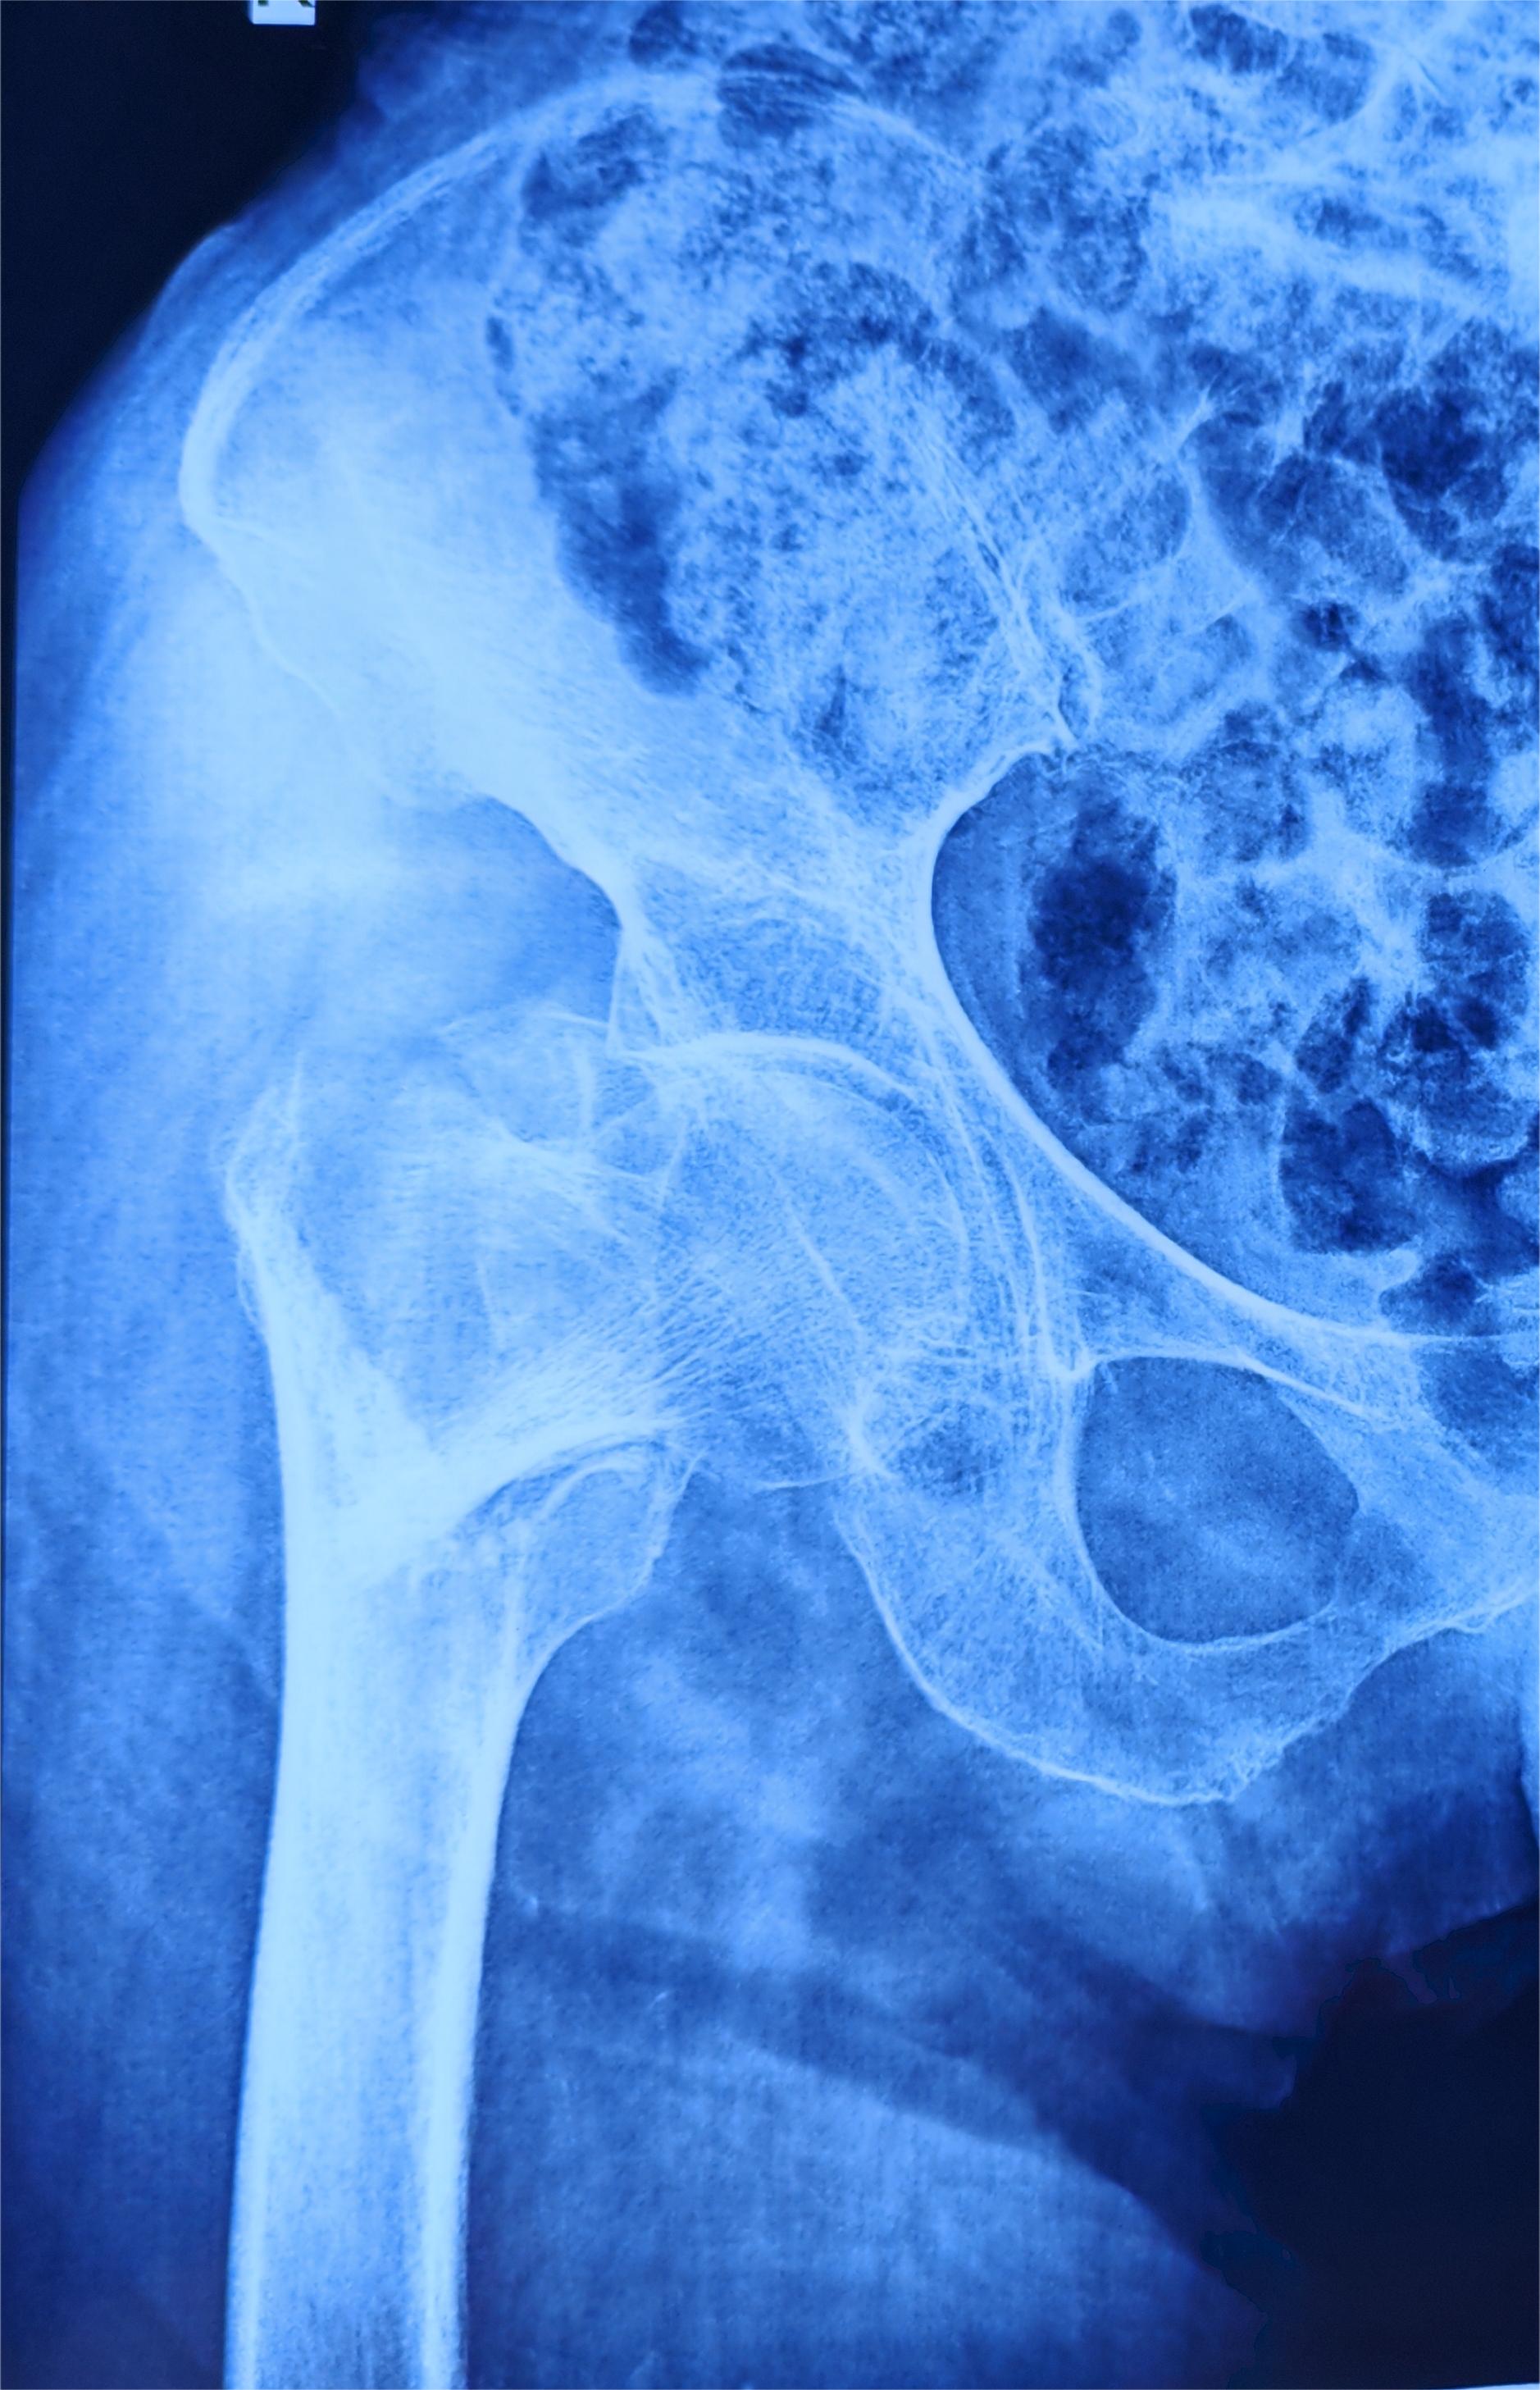

近日,87岁的王奶奶在家中不慎摔倒,无法动弹,卧床数日后疼痛加重,家人将老人送至临泽县人民医院检查,经过检查诊断其为“右侧髋部粉碎性骨折”,随即转入医院骨科进一步治疗。

入院后,经过进一步检查,王奶奶还患有慢阻肺、心脏病、高血压等疾病,手术风险较大,若不进行手术,长期卧床保守治疗又会引发肺部感染、下肢静脉血栓、压疮等危及生命。经过科室会诊讨论,决定为王奶奶实施髋部骨折闭合复位内固定手术,以最大限度地恢复王奶奶的关节功能,减少长期卧床带来的风险。